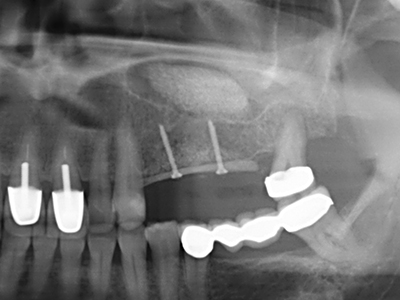

Aplicación: Preparación cerca del nervio

Como ya se ha mencionado, en el ámbito de la odontología conservadora también existen áreas en las que está indicada la cirugía piezoeléctrica. El uso de insertos de trabajo especiales facilita la representación del ápice radicular y, sobre todo en el área de los premolares inferiores y superiores, protege mejor los nervios y las mucosas del seno maxilar. En el caso de un cierre apical no estanco, los insertos de diamante acodados preparan de forma exacta y selectiva la cavidad de resección para el material de relleno retrógrado de la raíz. Gracias a la técnica de ultrasonidos, los insertos pueden presentar un diseño muy estilizado, lo que mejora la visión global y el tamaño de la cavidad de acceso. De este modo, en esta indicación, el uso de la cirugía por ultrasonidos se encuentra entre los métodos estándar para una apicectomía (Del Fabbro, Tsesis et al. 2010, Scarano, Artese et al. 2012).

Aplicación: Apicectomía

Si es preciso realizar intervenciones quirúrgicas en las que el hueso está en contacto directo con estructuras sensibles, como son los vasos sanguíneos o los nervios, los instrumentos rotativos presentan un enorme potencial de provocar lesiones iatrogénicas. Así, precisamente en la representación de nervios después de una lesión iatrogénica, o en el transcurso de la lateralización de un nervio para resecciones, reconstrucciones o incorporación de implantes, los equipos piezoeléctricos pueden resultar muy útiles para preparar la tapa ósea y retirar las partes de tejido duro cercanas al nervio (fig. 17-20). Por lo general, un ligero contacto del cordón nervioso con el inserto piezoeléctrico no tiene consecuencia alguna; ahora bien, un procedimiento poco cuidadoso con movimientos tipo sierra o piezas de trabajo sobre la base ósea aún existente puede provocar lesiones nerviosas temporales o incluso permanentes. Con todo, el riesgo de sufrir una lesión de este tipo se considera significativamente inferior que en los casos en los que se utilizan sierras y fresas (Pereira, Gealh et al. 2014).